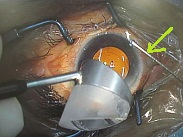

黄斑円孔の手術に関しては、?で記載しましたが、簡単におさらいすると、目の中に器械をいれて、内境界膜という網膜の表層の膜を剥離し、網膜を柔らかくします。その後、目の中に空気を入れてうつ伏せをすることで、円孔の周囲の網膜を浮力で引き寄せて、穴を閉じる。という方法です。